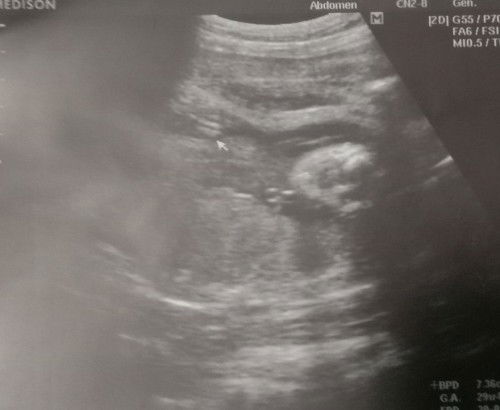

ช่วยดูทีค่ะแม่ๆ แบบนี้น้องผู้หญิงหรือผู้ชายคะ

#ขอบคุณล่วงหน้านะคะ #ท้องแรกค่ะ